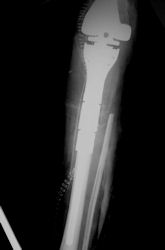

| Limb-sparing surgery for osteosarcoma of distal femur – Plain Xrays |

Examples of radical limb sparing surgeries for osteosarcomas in various anatomic locations (distal femur, proximal tibia, proximal humerus, scapula)

In each case, the tumor and bone from which it arose were resected. This required meticulous dissection, mobilization and preservation of adjacent pertinent neurovascular structures. In each case presented here, the defect was reconstructed with a special modular segmental tumor prosthesis. This also replaces the adjacent joint in many instances.

Postoperative X-Rays